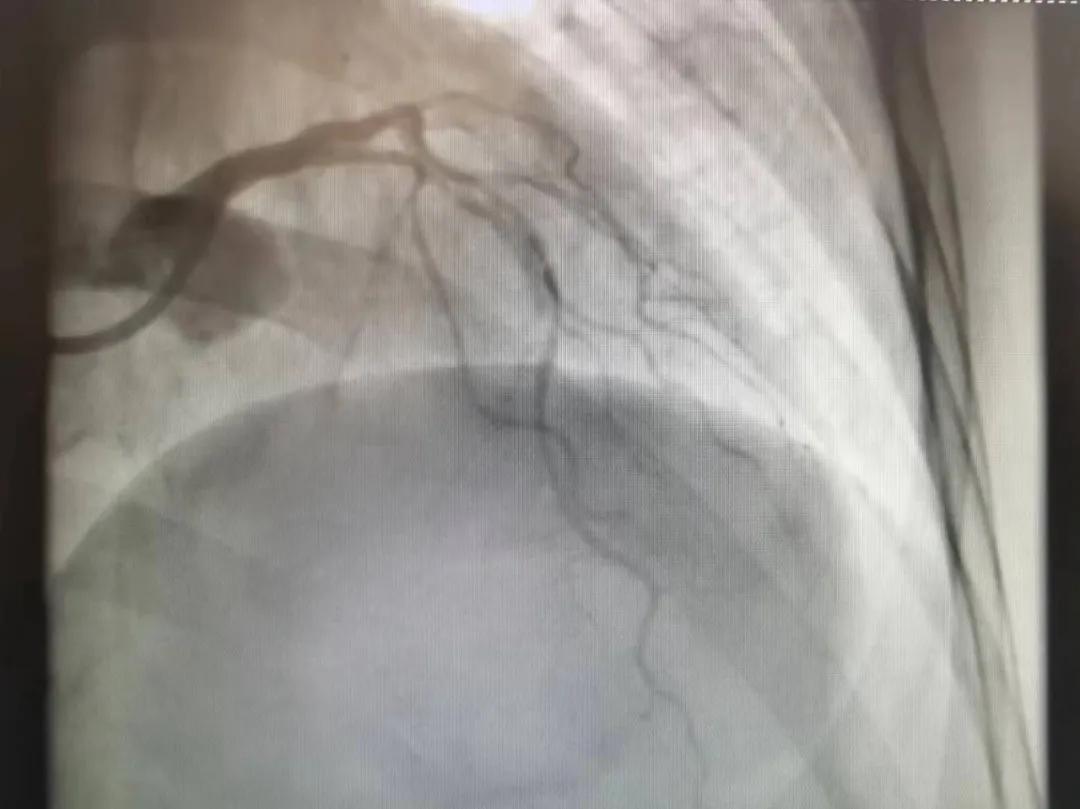

病人是位六十多歲的女性患者,有長(zhǎng)期高血壓病史,1個(gè)月前開始出現(xiàn)胸悶胸痛,口服藥物治療效果不佳,經(jīng)朋友介紹,來(lái)到市二院心血管內(nèi)科。入院后完善冠狀動(dòng)脈造影提示:前降支全程彌漫性狹窄伴鈣化,最重95%,回旋支狹窄約85%,右冠脈全程狹窄伴鈣化,最重60%。血管內(nèi)超聲顯示右冠脈開口面積3.36mm²,可見環(huán)形鈣化,考慮患者病變程度重、鈣化明顯,常規(guī)器械無(wú)法實(shí)現(xiàn)病變的良好預(yù)處理,且有很高的冠脈穿孔、血管夾層的風(fēng)險(xiǎn)。

術(shù)前